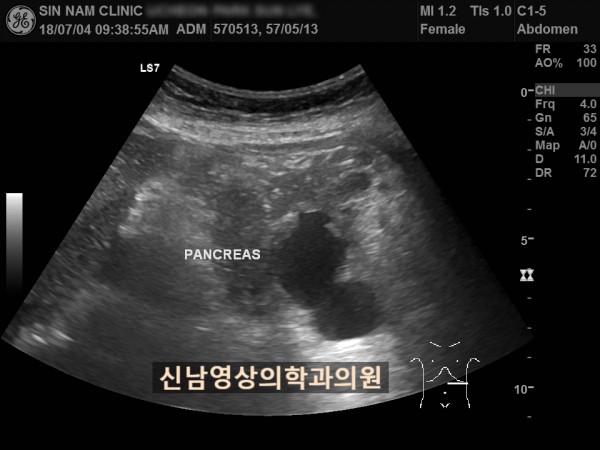

아래 환자분은 60대 여성분으로 식사만 하면 복통이 나타나서 내과에서 위 / 대장 내시경을 받으셨지만 정상으로 진단받았던 분으로 내과에서 복부 초음파검사를 했지만 이상 소견을 발견하지 못했던 분입니다.

복부 초음파 검사상 췌장꼬리(미부)에서 발생한 암으로 대장 장간막으로 전이가 되어서 대장내시경에서는 정상으로 확인되었고, 식사를 하면 장간막 전이때문에 장폐색 증상으로 복통이 발생하셨던 것으로 복막으로 전이가 진행되어 복수까지 있었습니다.

초음파 검사는 검사를 진행하는 사람의 숙련도에 따라 진단의 정확도가 결정되므로 영상의학과 전문의가 진료하는 병원에서 초음파 검사를 받아보실 것을 권합니다.